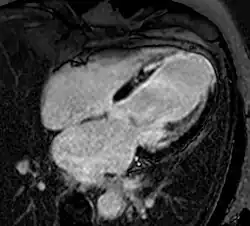

Atrial septal defect with dilation of the right ventricle by CMR